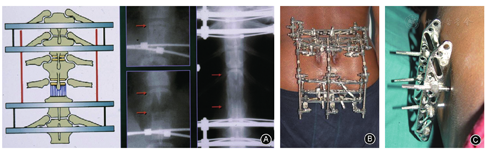

除骨科外广泛的应用于多个临床学科如脊柱外科(图5)、颌面外科(图6)、整形外科、血管外科等[27]。因此诞生了许多创新性的器械和技术[19,20,21,22]。基础研究方面,生长因子和促进骨愈合药物的应用也在肢体延长骨和软组织愈合中起到重要的作用[23,24]。